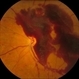

- Fundus Photography

- valsalva retinopathy, macular pre-retinal hemorrhage, smartphone fundus photography

- Dr.Prithvi Chandrakanth, Dr.Chandrakanth Malabar Nethralaya, Kozhikode.

- Trash To Treasure (T3) Retcam - Smartphone fundus Camera

- A 48-year-old male patient presented with complaints of diminution of vision in the left eye for 3 days. He gives a history of lifting heavy weight. Uncorrected visual acuity was 6/24 not improving with pin hole/glasses.